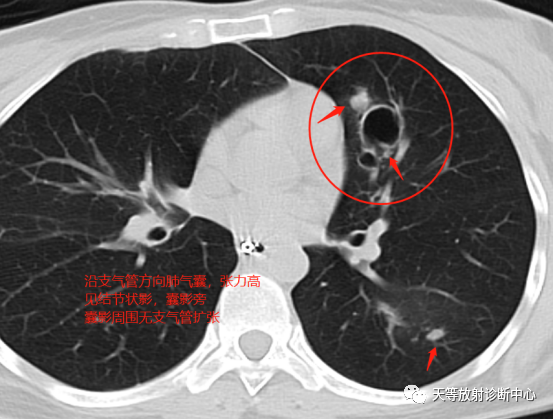

影像学表现:整体观察肺内多发病灶,散在分布,病灶的主要形态为:多发大小不等肺气囊、多发结节共同存在。

1、肺气囊大小不等,张力较大,圆形膨胀感强,周围可见大小不等结节影;

2、病灶主要沿支气管血管束方向分布,部分病灶达到胸膜下;

3、支气管间质增厚;

4、结节影大小不等,小的呈树芽征堆积,大的部分到达胸膜小,具有糊墙征,性格较温和。仔细观察病灶呈四边形、多边形,边缘刀切感,边界模糊。